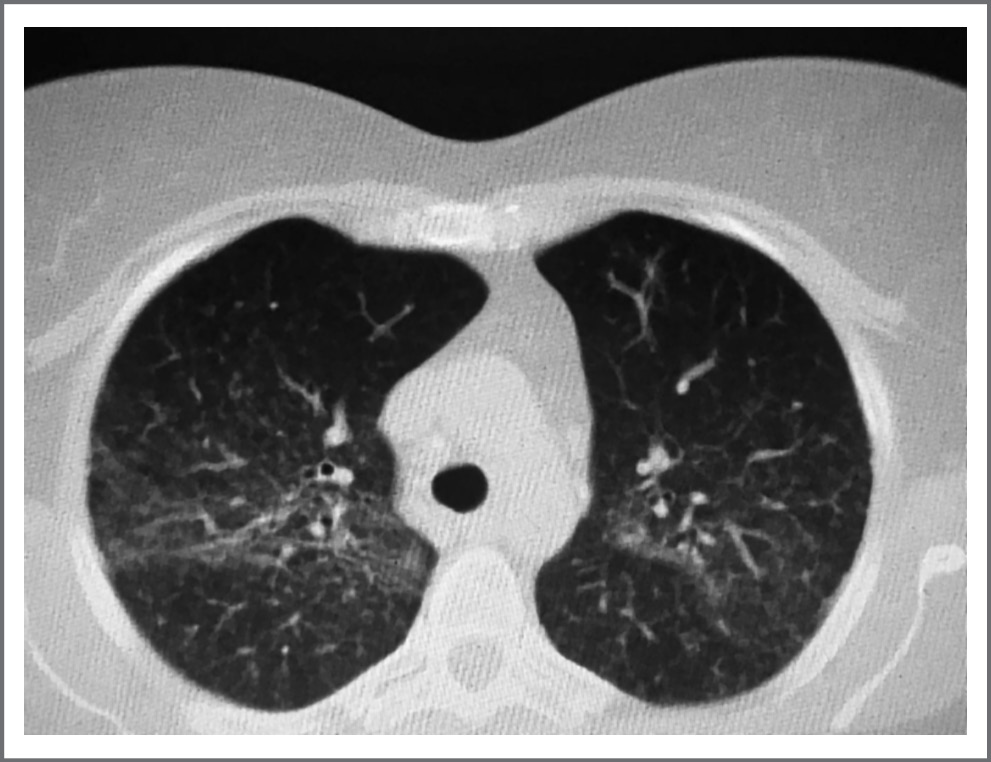

Первоначально при рентгенологическом исследовании изменения в легких расценены как двусторонняя полисегментарная пневмония, вновь назначены антибактериальные препараты, по-прежнему с незначительным эффектом. При мультиспиральной компьютерной томографии (КТ) органов грудной клетки (см. рисунок) обнаружена неравномерная пневматизация легочной паренхимы за счет дольковых просветлений и затемнений, формирующих картину «мозаичной перфузии». Отмечено выраженное неравномерное утолщение междольковых перегородок с деформацией легочного рисунка и нарушением архитектоники, кистозными изменениями (максимальным размером до 11 мм). Более выражены изменения в базальных отделах легких. Очаговых изменений в паренхиме легких не выявлено. Трахея и крупные бронхи прослеживаются на всем протяжении, не изменены. Выпота в плевральных полостях не визуализируется. Диафрагма не изменена. Средостение не смещено, структуры его дифференцированы. Сердце и магистральные сосуды без видимых изменений. Лимфатические узлы не увеличены. Костные структуры и мягкие ткани грудной клетки – без патологических изменений. КТ-картина соответствовала неспецифической интерстициальной пневмонии (НСИП) или гиперчувствительному пневмониту.

Изменения в легких у больной РА при приеме МТ: симптом «матового стекла», интерстициальный фиброз в базальных отделах

Учитывая исчезновение клинических симптомов поражения легких и положительную динамику при сравнении изображений КТ высокого разрешения (КТВР), можно диагностировать развитие у больной пневмотоксической реакции по типу острого пневмонита в результате приема МТ.